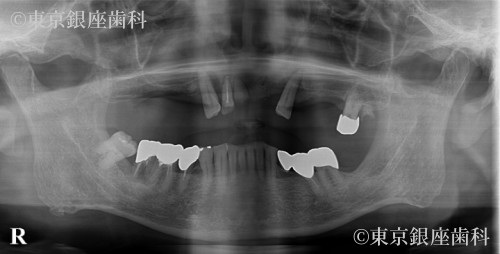

複数回の再埋入を経て骨と結合しづらい体質を克服した70歳代男性のインプラント症例

Before

骨と結合しづらい体質でインプラントが抜けることが続いたが、材料変更(HAコーティング等)で改善。2年半かけ安定した状態に。

上顎ワンデイインプラント+骨造成+サイナスリフト